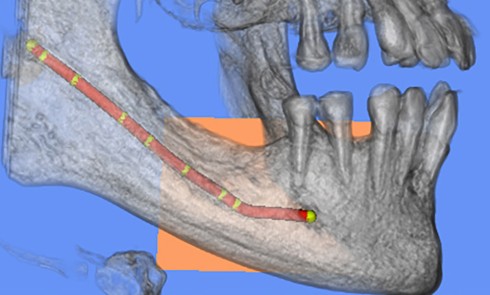

À propos d’une névralgie trigéminale intéressant deux territoires buccaux du nerf trijumeau

La névralgie du trijumeau (NT) est la plus répandue des névralgies, touchant la Ve paire de nerfs crâniens ou nerf...Nutrition, cavité et microbiote oral : un trio inséparable, indispensable pour notre santé